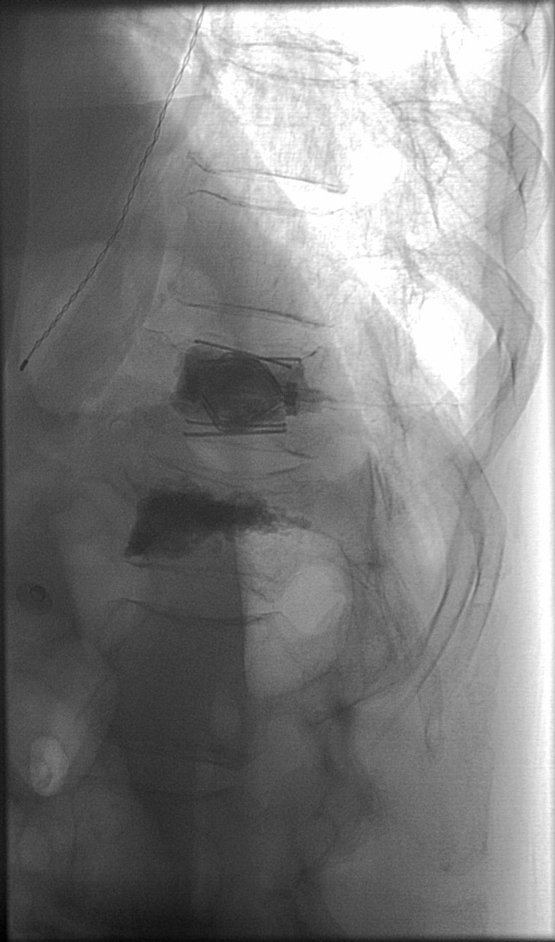

Stryker Spine Jack case at L4. First IR to place in Illinois! Patient feels great. Thanks to amazing Stryker support from Mike Villano. #Spinejack #jackit Stryke V The II #IRad #InterventionalRadiology #IamIR #IR #interventionalspine

74 y/o man with 2 week history of “miserable” pain. L4 inferior endplate compression fx. #SpineJack #PainFree post op Used 58s (BigBoys) #ItsBetterOn23rdStreet